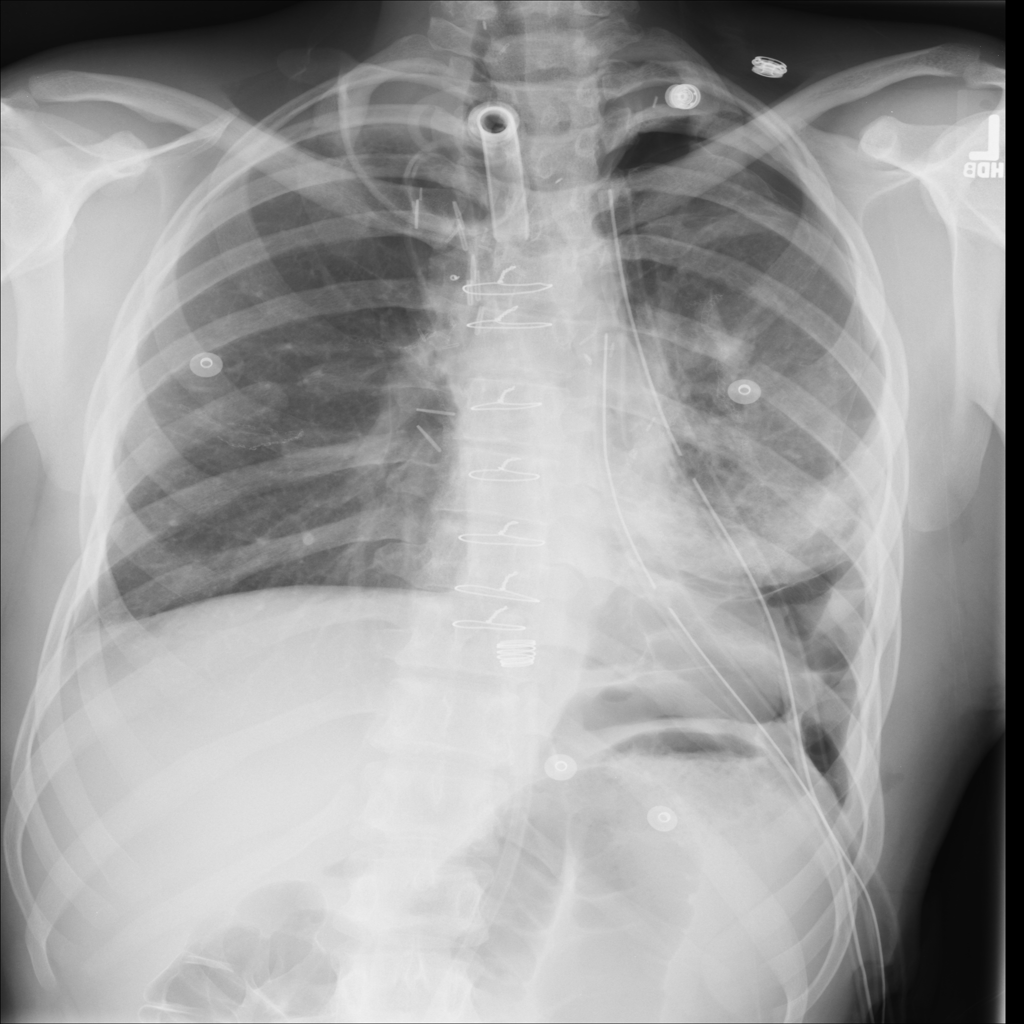

PAT-4639 · IMG-020Pneumothorax

PAT-4639 · IMG-020

PA